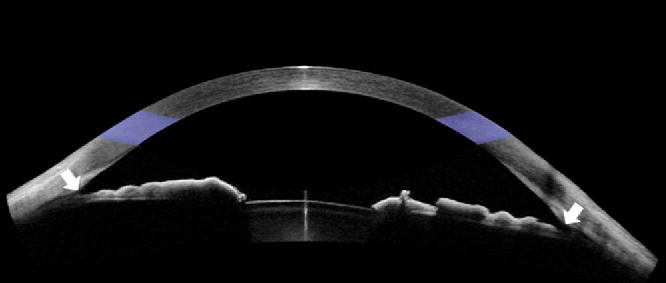

Anterior OCT captures information including corneal thickness (central and peripheral) and corneal transparency. It can also be focussed to give information about iris contour and anterior chamber angle patency.

Heidelberg Spectralis

Anterior OCT

Much like the Heidelberg Spectralis, this OCT captures corneal thickness and transparency data, iris contour and anterior chamber angle patency. However, it can also perform epithelial thickness mapping on the cornea.

Zeiss Cirrus 6000 Angioplex